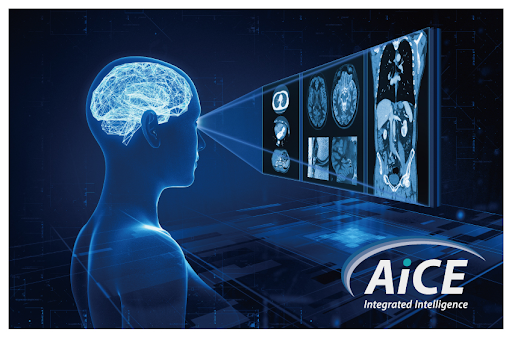

AiCE - это передовая технология основанная на нейронных сетях, которая направлена на уменьшение шума и усиление сигнала для получения четких изображений на высокой скорости.